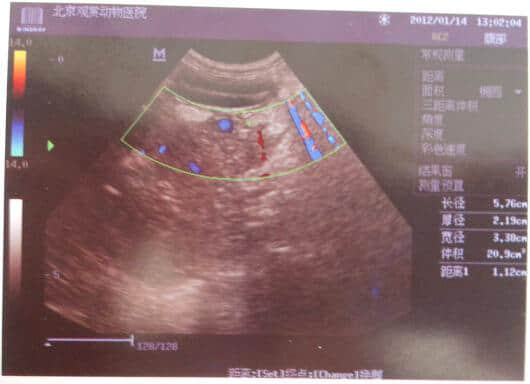

3.2 B超检查如下

从血液化验结果可发现WBC较高达42.62,血清脂肪酶高达4763,而淀粉酶却在正常值,这说明该犬胰腺炎已发病48或72小时以上。并据B超结果和临床症状可诊断为急性胰腺炎、脂肪肝和少量膀胱结石。其以胰腺炎为主。由于血糖较高不排除有糖尿病,建议复查血糖、尿糖。